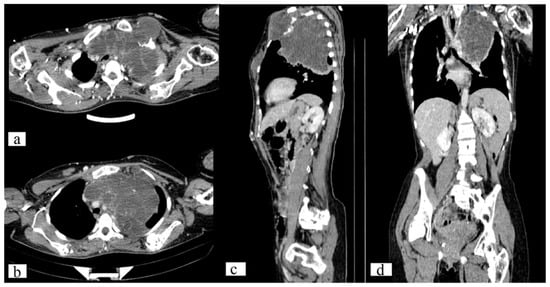

The CT scan of the chest revealed a large, well-circumscribed, destructive lytic lesion (11.7 × 13.1 × 11.2 mm) that had extended into the left lung and mediastinum, confirmed as chondroma by histological analysis. Additionally, a CT scan demonstrates numerous lesions on the sternum, left 5, 6, and 7 ribs, scapula, and humerus (on both sides) with a maximal size of 60 × 49 × 44 mm. There are numerous nodular lesions with calcifications on the anterior chest wall, the largest of which can measure up to 2.3 × 1.0 cm (Figure 3).

Figure 3. Axial (a,b), sagittal (c) and frontal (d) CT scan of the chest demonstrates a well-circumscribed, destructive lytic lesion of the left 1st rib (11.7 × 13.1 × 11.2 mm) and sternum (60 × 49 × 44 mm).